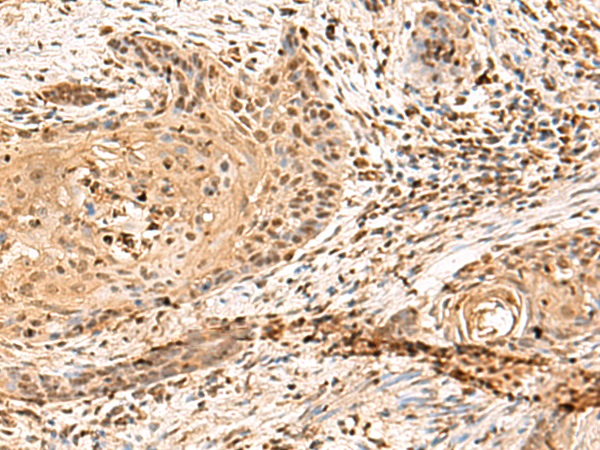

分类: 科研抗体货号: P10113别名: EIF2B; EIF-2Bbeta应用: IHC反应种属: Human, Mouse, Rat